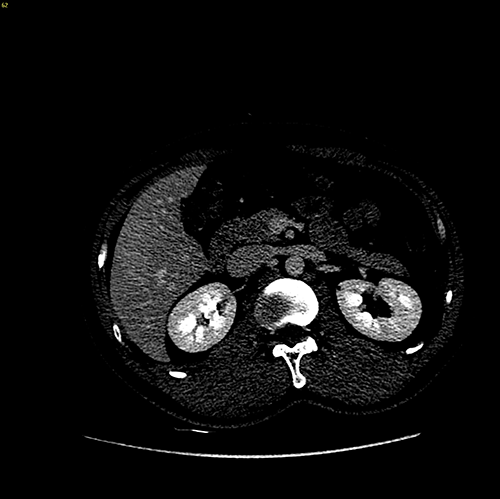

S6肝癌 胆囊结石--腹腔镜右肝部分切除 胆囊切除